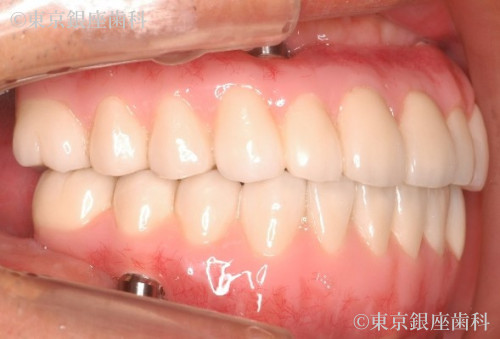

そもそも受け口だったので、ワンデイインプラントの人工歯によって受け口も改善する計画を立てました。

ワンデイインプラントの特徴である少ないインプラントの本数による全顎的な口腔機能の回復と、人工歯によって受け口の改善もできた口腔機能と審美が回復した症例です。